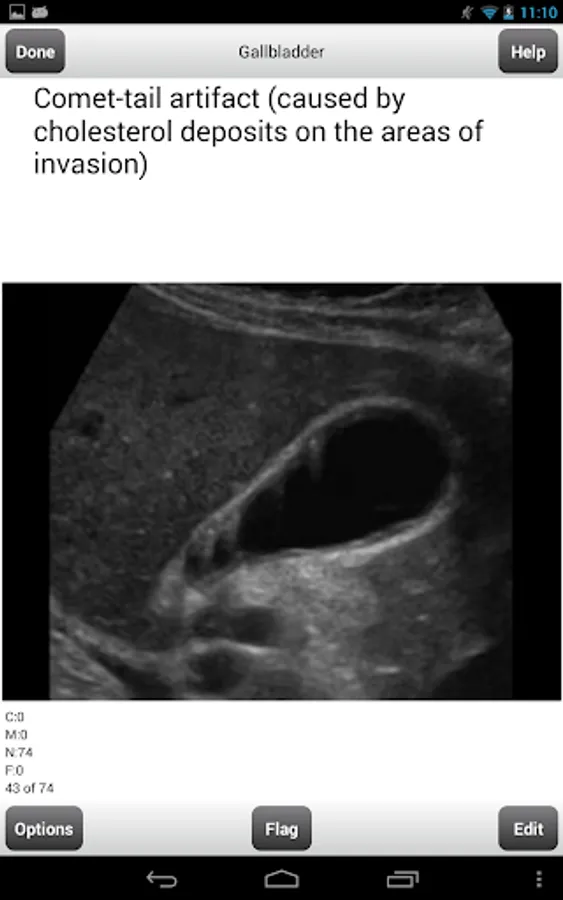

Gallbladder - 74 flashcards